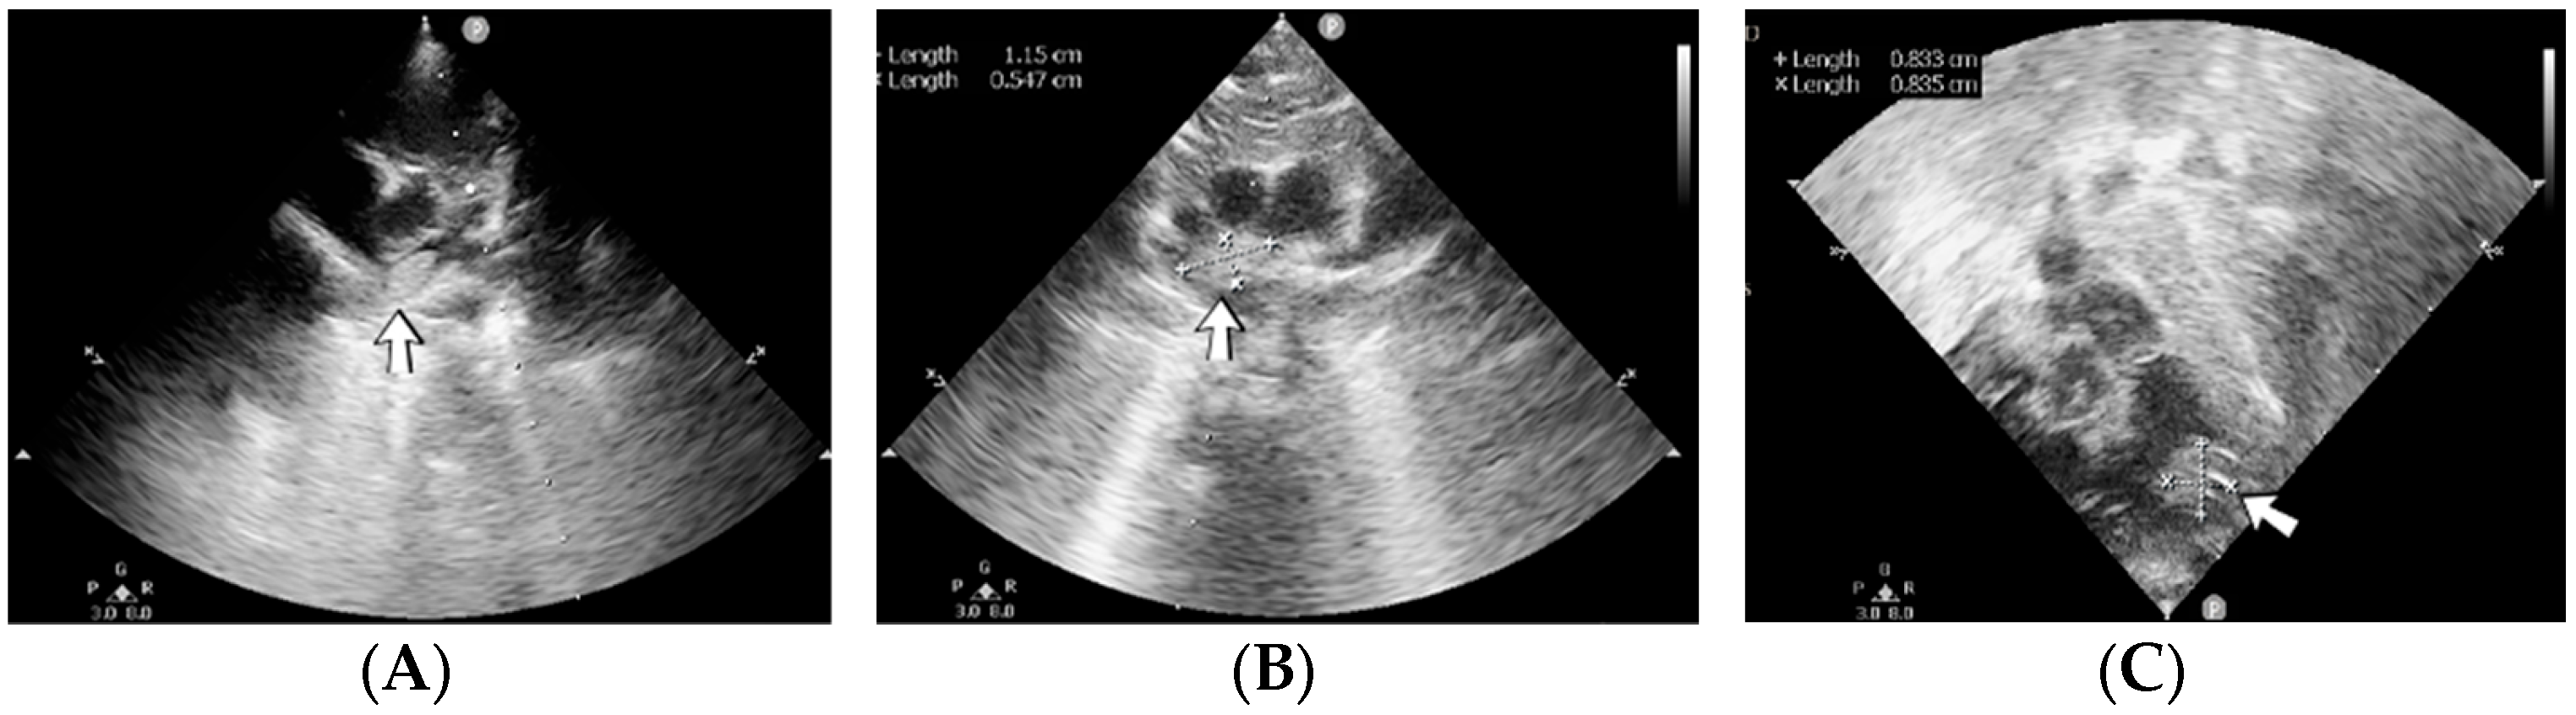

4.36. Case No. 36—Postnatal Intracardiac Thrombosis

A 7-week-old male infant (36 weeks, 2.50 kg), the first twin from a twin pregnancy, presented with a complex congenital cardiac malformation for an elective surgical procedure (Blalock–Taussig shunt). Heparin infusion for the shunt was started immediately after the intervention and anticoagulation was continued with enoxaparin due to good clinical condition. Then, 18 days after the procedure, a routine cardiovascular ultrasound revealed a thrombus in the left ventricle (Figure 16). The laboratory studies showed leukocytosis, highly elevated c-reactive protein, and modified coagulation tests (due to anticoagulant treatment). Continuous heparin infusion was reinitiated, but multiple intracardiac thrombi were detected during the following days. Treatment with alteplase was also started, but the patient’s condition continued deteriorating, leading to a negative outcome due to cardiac failure.

Figure 16.

Intracardiac thrombosis identified on cardiac ultrasound: left atrium and ventricle (A), left ventricle (B), apex (C).

Genetic testing confirmed inherited thrombophilia, with positive PAI-1 4G/5G promoter, MTHFR A1298C homozygous gene mutations, and Antithrombin and Protein C deficiencies. There was no known family history of thrombophilia. The mother had a previous therapeutic abortion due to a prenatal diagnosis of a complex congenital cardiac malformation.